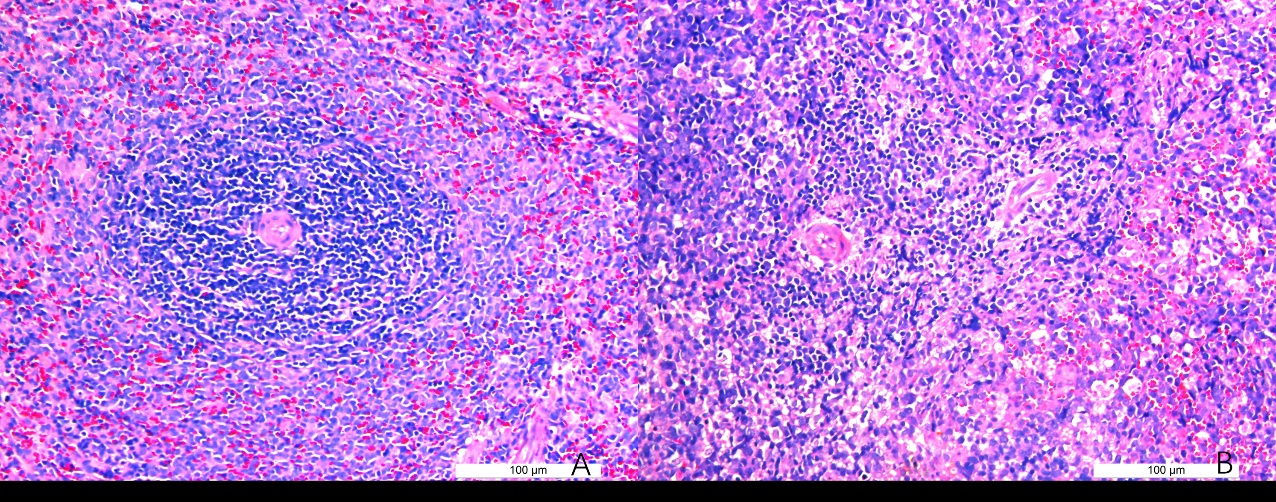

2 结果48 h各组病理结果,对照组脾组织结构正常(见图 1A )。脓毒症组脾组织见白髓结构破坏,红白髓交界模糊,多量组织细胞浸润,红髓充血(见图 1B)。差异mRNA的Volcano-plot分布图(见图 2)。相比于对照组,24 h时脓毒症组脾组织mRNA表达上调的有1 030个,下调的有935个[5];48 h组表达上调的有1 354个,下调的有1 763个。差异mRNA的聚类情况(见图 3)。GO功能分类结果(见图 4)。脓毒症大鼠脾组织部分通路相关基因表达情况(见图 5、6):脓毒症大鼠24 h,48 h脾组织关于细胞因子及其受体相互作用通路相关基因的分布图(见图 7,图 8)。脓毒症大鼠24 h,48 h脾组织关于细胞凋亡相关通路的基因分布图(见图 9,图 10)。

| 图 1 正常大鼠及脓毒症组大鼠48 h脾组织病理切片图 |

早期过度炎症反应、晚期免疫抑制系脓毒症的重要机制之一[6-7]。脾脏为人体免疫器官,在血源性抗原出现时,负责启动免疫反应[9]。脓毒症时SIRS反应可引起脾功能障碍[10]。本研究发现脓毒症48 h大鼠脾组织白髓结构破坏,红白髓交界模糊,其结构改变可能影响其免疫功能。既往对脓毒症大鼠24 h采用基因芯片分析发现部分基因表达异常[11]。若能进一步研究其早晚期的相关基因表达变化也许对脓毒症脾功能障碍有进一步的诠释。本研究采用RNA-seq技术对脓毒症大鼠早晚期脾组织行mRNA检测,是既往研究的深入,发现脓毒症早期组脾组织基因上下调数远少于晚期组,如脓毒症24 h组脾组织mRNA上调数1 030个,下调数935个,而48 h组mRNA上调数1 354个,下调数1 763个,差异明显(见图 2),符合疾病的发展过程。从图 3看,脓毒症24 h、48 h部分区域从红色趋于变浅甚至变蓝,浅蓝趋于蓝色,直观的反应脓毒症时脾脏基因表达量变化情况。从GO功能分类结果(图 4)得知,cellular processes、Environmental informationProcessing、Genetic Information Processing、Human Diseases、Metabolism、Organismal Systems相关功能基因随时间发展出现差异表达数为上升趋势。进而我们对其分析发现,脓毒症早晚期脾mRNA出现变化主要涉及细胞因子与其受体相互作用、IL-17、T细胞受体、TH1、TH2细胞分化、TNF、Toll受体、凋亡等相关信号通路。研究显示,脓毒症晚期免疫抑制可能是脓毒症患者死亡的主要原因,免疫治疗可能是未来一大趋势[12-15]。本文拟从炎症反应与细胞凋亡相关通路来阐述脓毒症脾功能障碍的相关机制。